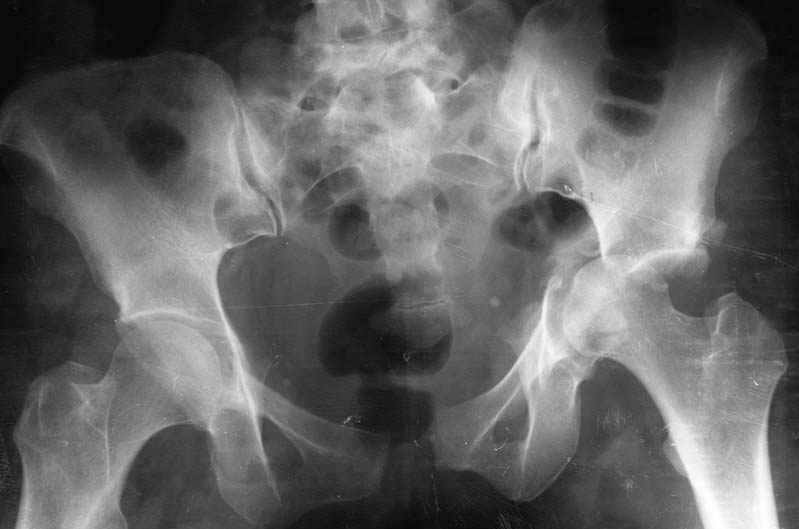

Таз - 2

Мужчина, 34 года. Травма производственнная.

Какова ваша хирургическая тактика в подобном случае?

В день травмы - автономное скелетное вытяжекние (сдавление крыльев таза + дистракция бедра для спасения головки от острого края остатков свода), после стабилизации состояния синтез пластинами впадины и лона.